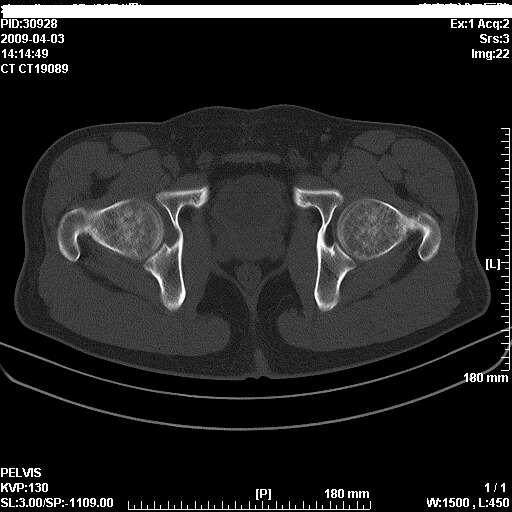

以下是引用随光逐影在2009-4-4 15:13:00的发言:[br]考虑双侧股骨头无菌性坏死;建议行mri检查进一步明确诊断。

以下是引用余辉在2009-4-4 14:22:00的发言:[br]双侧髋关节诸构成骨未见明显异常.必要时mr检查[br]患者症状已有两年,可能要同时从其他方面找原因,个人觉得不排除双侧骶髂关节有问题,建议ct检查